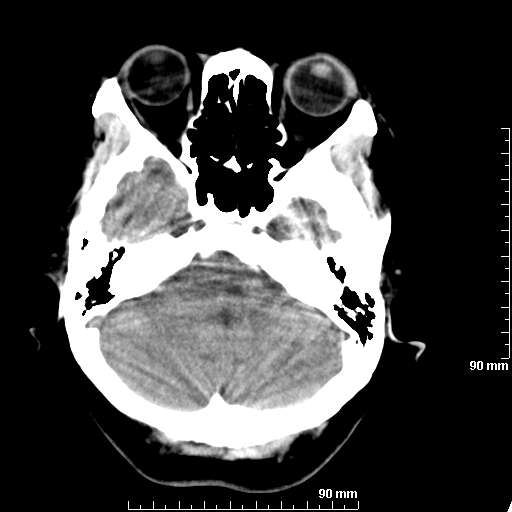

我院西门子单排CT由于一零件受损而产生的伪影.

哈哈,都不是。是虑线器fiter裂损。大家没想到吧。

哦,跟脑出血有点像哦

形状不规则,边缘模糊。比较特殊的一种伪影哈!

这种伪影很常见!伪影应该是在视野的中心的。

西门子的虑线器fiter裂损这才是很难见的问题,GE的最常见

虑线器老化,中间崩裂一块掉了